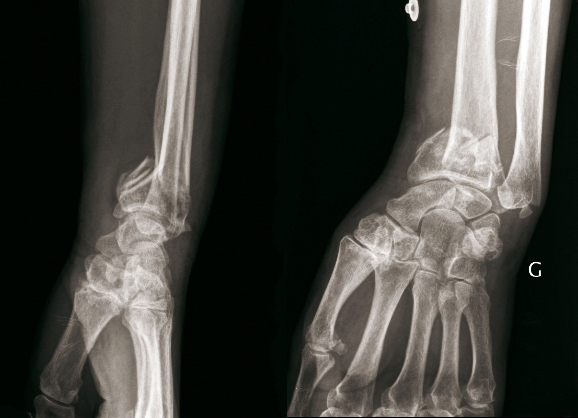

© Henry Coudane, Frédéric Éloy (La Revue du Praticien) Fracture extra-articulaire à déplacement antérieur. (À gauche) Radio de profil. (À droite) Radio de face.